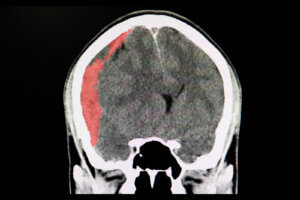

Distinguir un ACV isquémico de uno hemorrágico con base en la sintomatología es muy difícil. Por ello, en todos los casos se requiere una visita a urgencias, donde se realizarán pruebas como tomografías axiales computarizadas, arteriografías e imágenes por resonancia magnética.